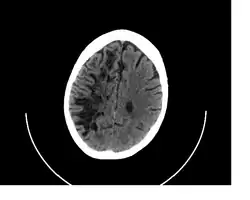

![]() A perivascular space as seen on CT | |

A perivascular space, also known as a Virchow–Robin space, is a fluid-filled space surrounding certain blood vessels in several organs, including the brain,[1] potentially having an immunological function, but more broadly a dispersive role for neural and blood-derived messengers.[2] The brain pia mater is reflected from the surface of the brain onto the surface of blood vessels in the subarachnoid space. In the brain, perivascular cuffs are regions of leukocyte aggregation in the perivascular spaces, usually found in patients with viral encephalitis.

In humans, perivascular spaces surround arteries and veins can usually be seen as areas of dilatation on MRI images. While many normal brains will show a few dilated spaces, an increase in these spaces may correlate with the incidence of several neurodegenerative diseases, making the spaces a topic of research.[4]

Perivascular spaces are most commonly located in the basal ganglia and white matter of the cerebrum, and along the optic tract.[13] The ideal method used to visualize perivascular spaces is T2-weighted MRI. The MR images of other neurological disorders can be similar to those of the dilated spaces. These disorders are:[7]

Perivascular spaces are distinguished on an MRI by several key features. The spaces appear as distinct round or oval entities with a signal intensity visually equivalent to that of cerebrospinal fluid in the subarachnoid space.[7][14][15] In addition, a perivascular space has no mass effect and is located along the blood vessel around which it forms.[14]